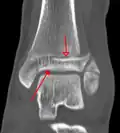

| Fracture of both sides of the ankle with dislocation as seen on anteroposterior X-ray. (1) fibula, (2) tibia, (arrow) medial malleolus, (arrowhead) lateral malleolus | |